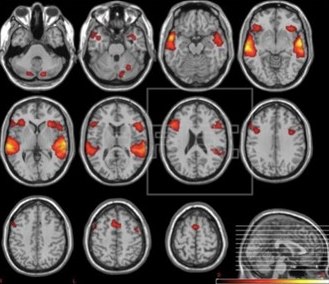

resonancia magnética

Resonancia magnética que permite monitorizar la actividad cerebral.

La Medicina Nuclear es una especialidad de la medicina que utiliza aplicaciones de la Física Nuclear para el diagnóstico y tratamiento de enfermedades. En la parte diagnóstica podemos encontrar técnicas como la Tomografía Computerizada (TC), la Resonancia Magnética Nuclear o la Tomografía por Emisión de Positrones (PET) que tienen como objetivo el estudio y la identificación de las posibles causas de una enfermedad.

Por otro lado, en la parte de tratamiento, encontramos técnicas como la radioterapia que emplean altas dosis de radiación para destruir células cancerosas y reducir tumores.